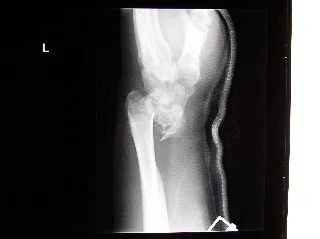

At that time, I did not have any health insurance which meant I did not want to call for an ambulance. That day I had drove to the climbing spot which was about a 15-minute walk to my car. Being stubborn and cash light meant that I gave Chandra (Chandra was a fellow ski instructor and friend) my car keys and she drove to the ER of the nearest hospital. To put me back together, I required 10 screws and a plate in my left arm, 6 staples in my head, and a 3 day stay at St. Luke’s Regional Medical Center before I was stable enough to be released back to my 500 square foot basement apartment in the trendy north end of Boise. This would become my official welcoming to the world of chronic, I just didn’t know that at the time.

As silly and odd as this might sound, this Eggo incident in my life ranks as one of my proudest accomplishments. Considering the amount of pain and bruising (the bruising from my fall was so bad that the resident working that night in the ER thought I had ruptured my spleen. He was so convinced that I was in a CT scan for my spleen before I had one on my neck and left arm) I had developed after the fall there would have been no shame in asking a parent or friend to pull the toaster out from the bottom cupboard. In fact, I’m guessing 20 risk analysis specialists would have agreed that I should wait for someone due to the extent of my injuries. Maybe it was all the drugs still running through my system, maybe it is just who I am as a person, but problem solving that moment seemed critical for me to undertake as part of my patient journey. I needed to accept that for the rest of my life, routine tasks like getting a toaster out were no longer routine. Problem solving for me now meant both how might I scale Mount Everest and how might I eat breakfast today.

My left wrist the night I fell rock climbing.